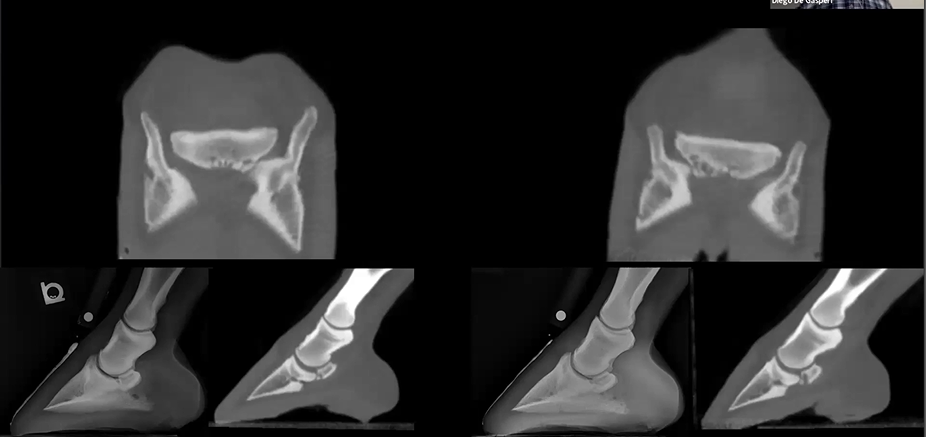

Read MoreThis horse had a history of hock arthritis and lameness. CT images show several cyst-like lesions in the third tarsal bone and the proximal aspect of the third metatarsal bone. The arthritis was noticed mostly in the right hind but also in the left hind with narrowing in the joint space. Featured: Dr. Diego De Gasperi, University of Wisconsin-Madison